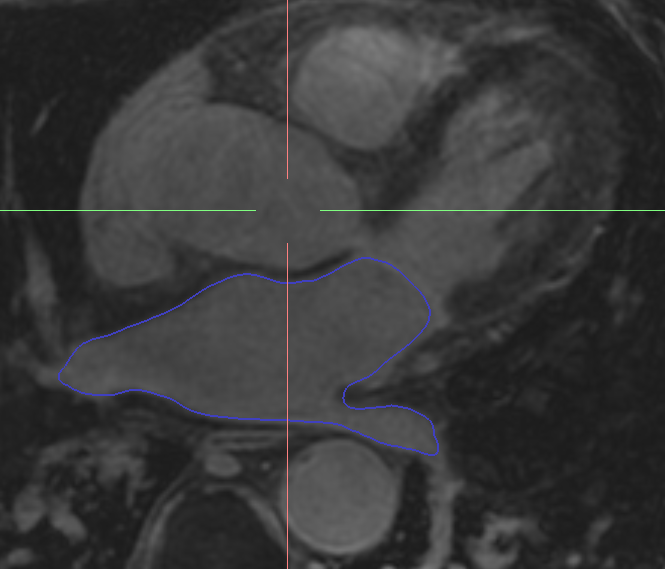

Colour inside the lines… and the left atrium! Improving step by step: segmentation Remember when you were 4 and you used to draw and paint pictures of cute animals or superheroes? Remember what your parents and your teachers used to tell you? “Colour inside the lines, do not cross the lines when you are painting!”. …